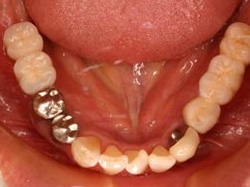

両側5歯症例

両側5歯症例両側5歯症例両側5歯症例 主訴-義歯のバネが壊れて手前の歯が痛んできた。 術前(旧義歯装着、鏡像) 術前(下顎粘膜面、鏡像)術前(下顎粘膜面、鏡像)術前(下顎粘膜面、鏡像) 術前レントゲン術前レントゲン術前レントゲン 術前口腔内(正面観)術前口腔内(正面観)術前口腔内(正面観)

術後(鏡像)術後(鏡像)術後(鏡像) 術後口腔内(正面観)術後口腔内(正面観)術後口腔内(正面観)もう入れ歯は要らなくなりました。 術後レントゲン術後レントゲン術後レントゲン